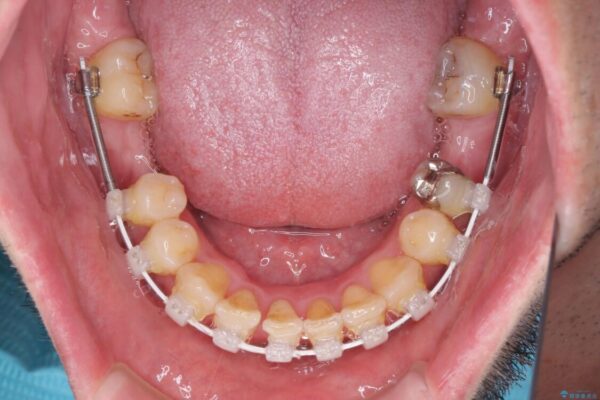

治療途中

• 割れてしまった奥歯とデコボコの前歯 矯正治療とインプラント治療 治療途中画像